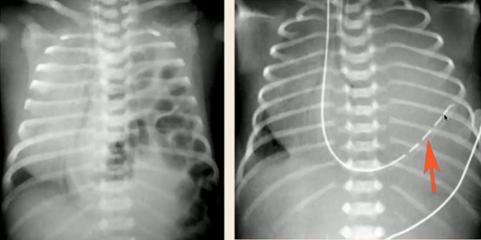

图22.仰卧位气胸(左):深沟征(大片肺野透亮,纹理消失;肋膈角较对侧深);仰卧位纵隔气胸(右):天使翅膀征(胸腺边界特别清晰,可有“漂浮感”)③下呼吸道异物

图23.仰卧位或站立位时右肺过度充气(肺野透亮度高),右侧卧位后透亮度无变化④先天性肺不张/肺发育不良

图24.先天性肺发育不良:(左)左侧无肺组织,肺不张;右侧过度充气,纵隔向患侧偏移;(右)CT可见支气管盲端先天性肺发育不良可分为原发性和继发性,其中继发性可由胸外挤压(羊水过少)或胸内挤压(先天性膈疝等)原因所致。

图25.先天性膈疝膈疝:(左)纵隔右移,左侧肺野见充气肠管;(右)胃管位于胸腔内文中影像资料来源于: